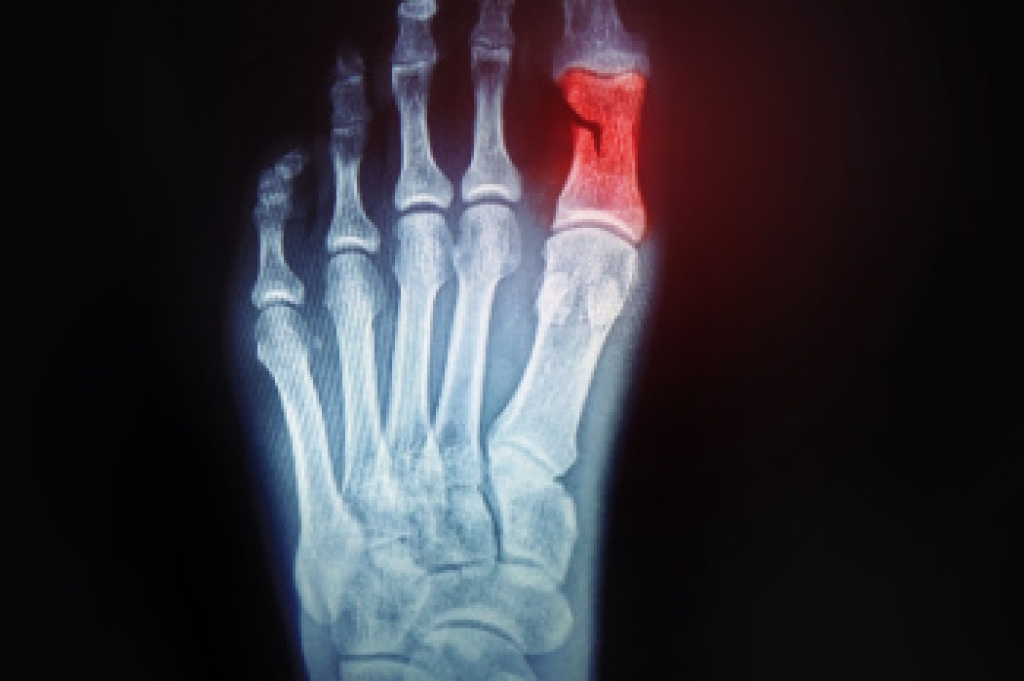

Key Signs to Look for in a Broken Toe

Identifying a broken toe is important for timely treatment and recovery. One of the primary signs is a noticeable change in the toe's shape, as it may appear misaligned, crooked, or deformed. Severe pain is another common indicator, often sharp and intense at the moment of injury and persisting with movement. The affected toe might also show swelling and bruising, with discoloration appearing as a dark purple or blue hue. In some cases, there may be difficulty or discomfort when trying to move the toe. Prompt medical evaluation is essential for proper diagnosis and treatment, which may include rest, immobilization, or in severe cases, surgical intervention. If you have broken your toe, it is suggested that you consult a podiatrist who can offer you the correct treatment.

A broken toe occurs when one or more of the toe bones of the foot are broken after an injury. Injuries such as stubbing your toe or dropping a heavy object on it may cause a toe fracture.